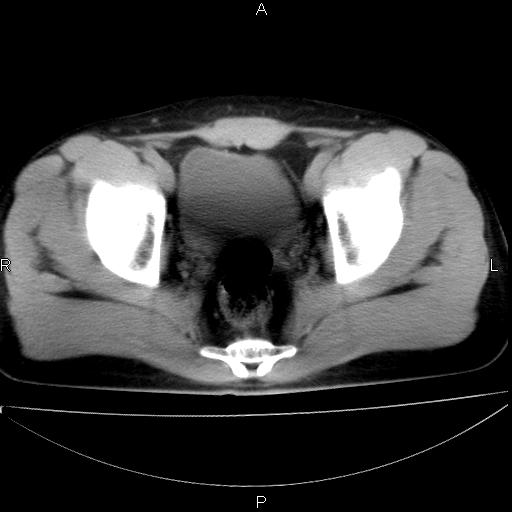

标题: CT29462:双测输尿管扩张

男 25岁 自述 尿频尿急,排尿困难20多天.无腰痛, b超说左肾盂轻度积水,左输尿管上端扩张.未见结石影. ct我看双侧肾盂轻度积水,双输尿管上端都扩张,大家看看能看见结石吗?

双输尿管扩张下端未见高密度结石和输尿管晕轮征,不好说是结石.增强后如何?

双肾轻度积水,未见明确结石,薄层对结石检出率较高。

双侧输尿管上端扩张,未见明确结石,可进一步ivp检查。